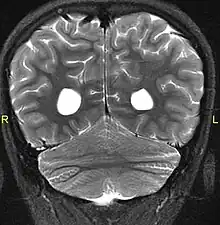

Aside from the physical characteristics of the eyes there is also less sensation in the eyes when stimulated.[4] The eyes also show low motor control (ataxia).[4] Along with ataxia comes a lack of coordination or ability to judge the distance of objects (dysmetria).[6] MRIs show a constant feature of rhombencephalosynapsis–a condition marked by the absence or partial absence of the cerebellar vermis and varying degrees of fusion in the cerebellum in every case of Gómez–López-Hernández syndrome.[4][7][8] Also absent are the trigeminal nerve of the trigeminal cave and the foramen rotundum, causing abnormal sensations on the forehead and the corneas.[6][8] One Gómez–López-Hernández syndrome case in Japan also presents fever-induced seizures.[9] Others may or may not present with non-fever-induced seizures.[4] Malformations of motor centers in the brain cause reduced muscle strength (hypotonia).[8] Eleven of fifteen people in one study showed moderate-to-severe intellectual disability.[6] In cases where it has been noted, head nodding is present.[6] Hydrocephalus and enlargement of the ventricular system is consistently present.[6] A reduced corpus callosum is present in some cases (agenesis of the corpus callosum).[6]